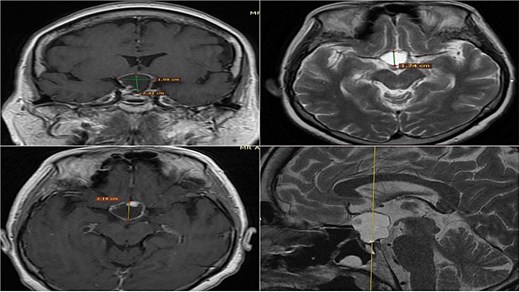

A 71-year-old woman who gradually began with bitemporal hemianopia, progressing to amaurosis of the right eye, adding diabetes insipidus. An MRI study obtained the following images (Fig. 1). 3D reconstruction was performed by manual segmentation to obtain the anatomy of the tumor and its vascular relationships. For this segmentation, it was necessary to splice T2, T1, Contrast, and 3D TOF sequences (Fig. 2). The importance of the reconstruction lies in being able to adequately observe most of the cerebral blood circle and its relationships with the tumor. At the time of carrying out the transnasal resection surgery and keeping in mind the proximity of the anterior communicating artery with the dorso-ventral region of the tumor, the capsule was resected with excessive caution to avoid generating excessive traction and thus avoiding injuries—important vascular (Fig. 3).

MRI of sellar region tumor in contrasted T2 and T1 sequences in axial, coronal and sagittal sections.

Contrast-enhanced T1 MRI of pituitary marcoadenoma. Multiplanar conventional geometric volumetry.